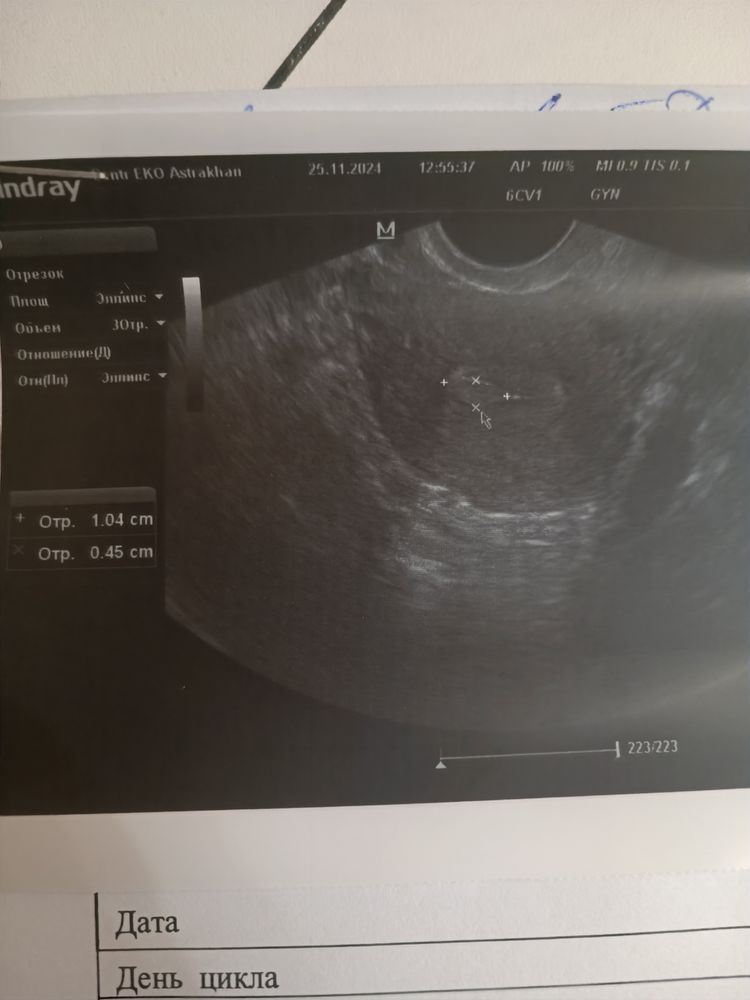

Полип?

Похоже на полип.

на снимке полип классический в полости